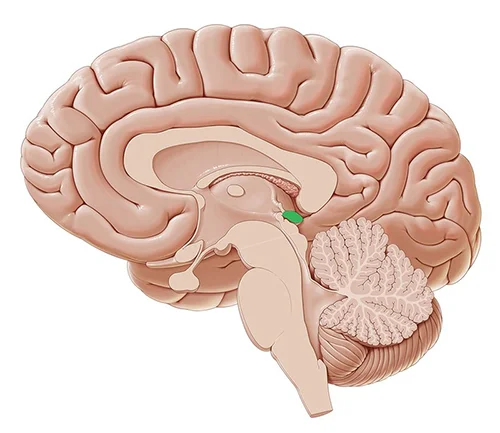

Glandula Pineal

La glándula pineal, también conocida como cuerpo pineal, conarium o epífisis cerebral es una pequeña glándula endocrina en el cerebro de los vertebrados. Produce melatonina, una hormona derivada de la serotonina que afecta a la modulación de los patrones del sueño, tanto a los ritmos circadianos como estacionales.

El sueño es un estado fisiológico propio del ser humano y otros animales. Está regulado por la glándula pineal, situada en la base del cerebro, que produce una sustancia química fundamental para los procesos del sueño: la melatonina. Su producción y liberación aumenta por la noche y disminuye durante el día, por lo que las variaciones de la cantidad de melatonina en sangre regulan el ritmo circadiano del sueño-vigilia, que suele adaptarse al horario solar.